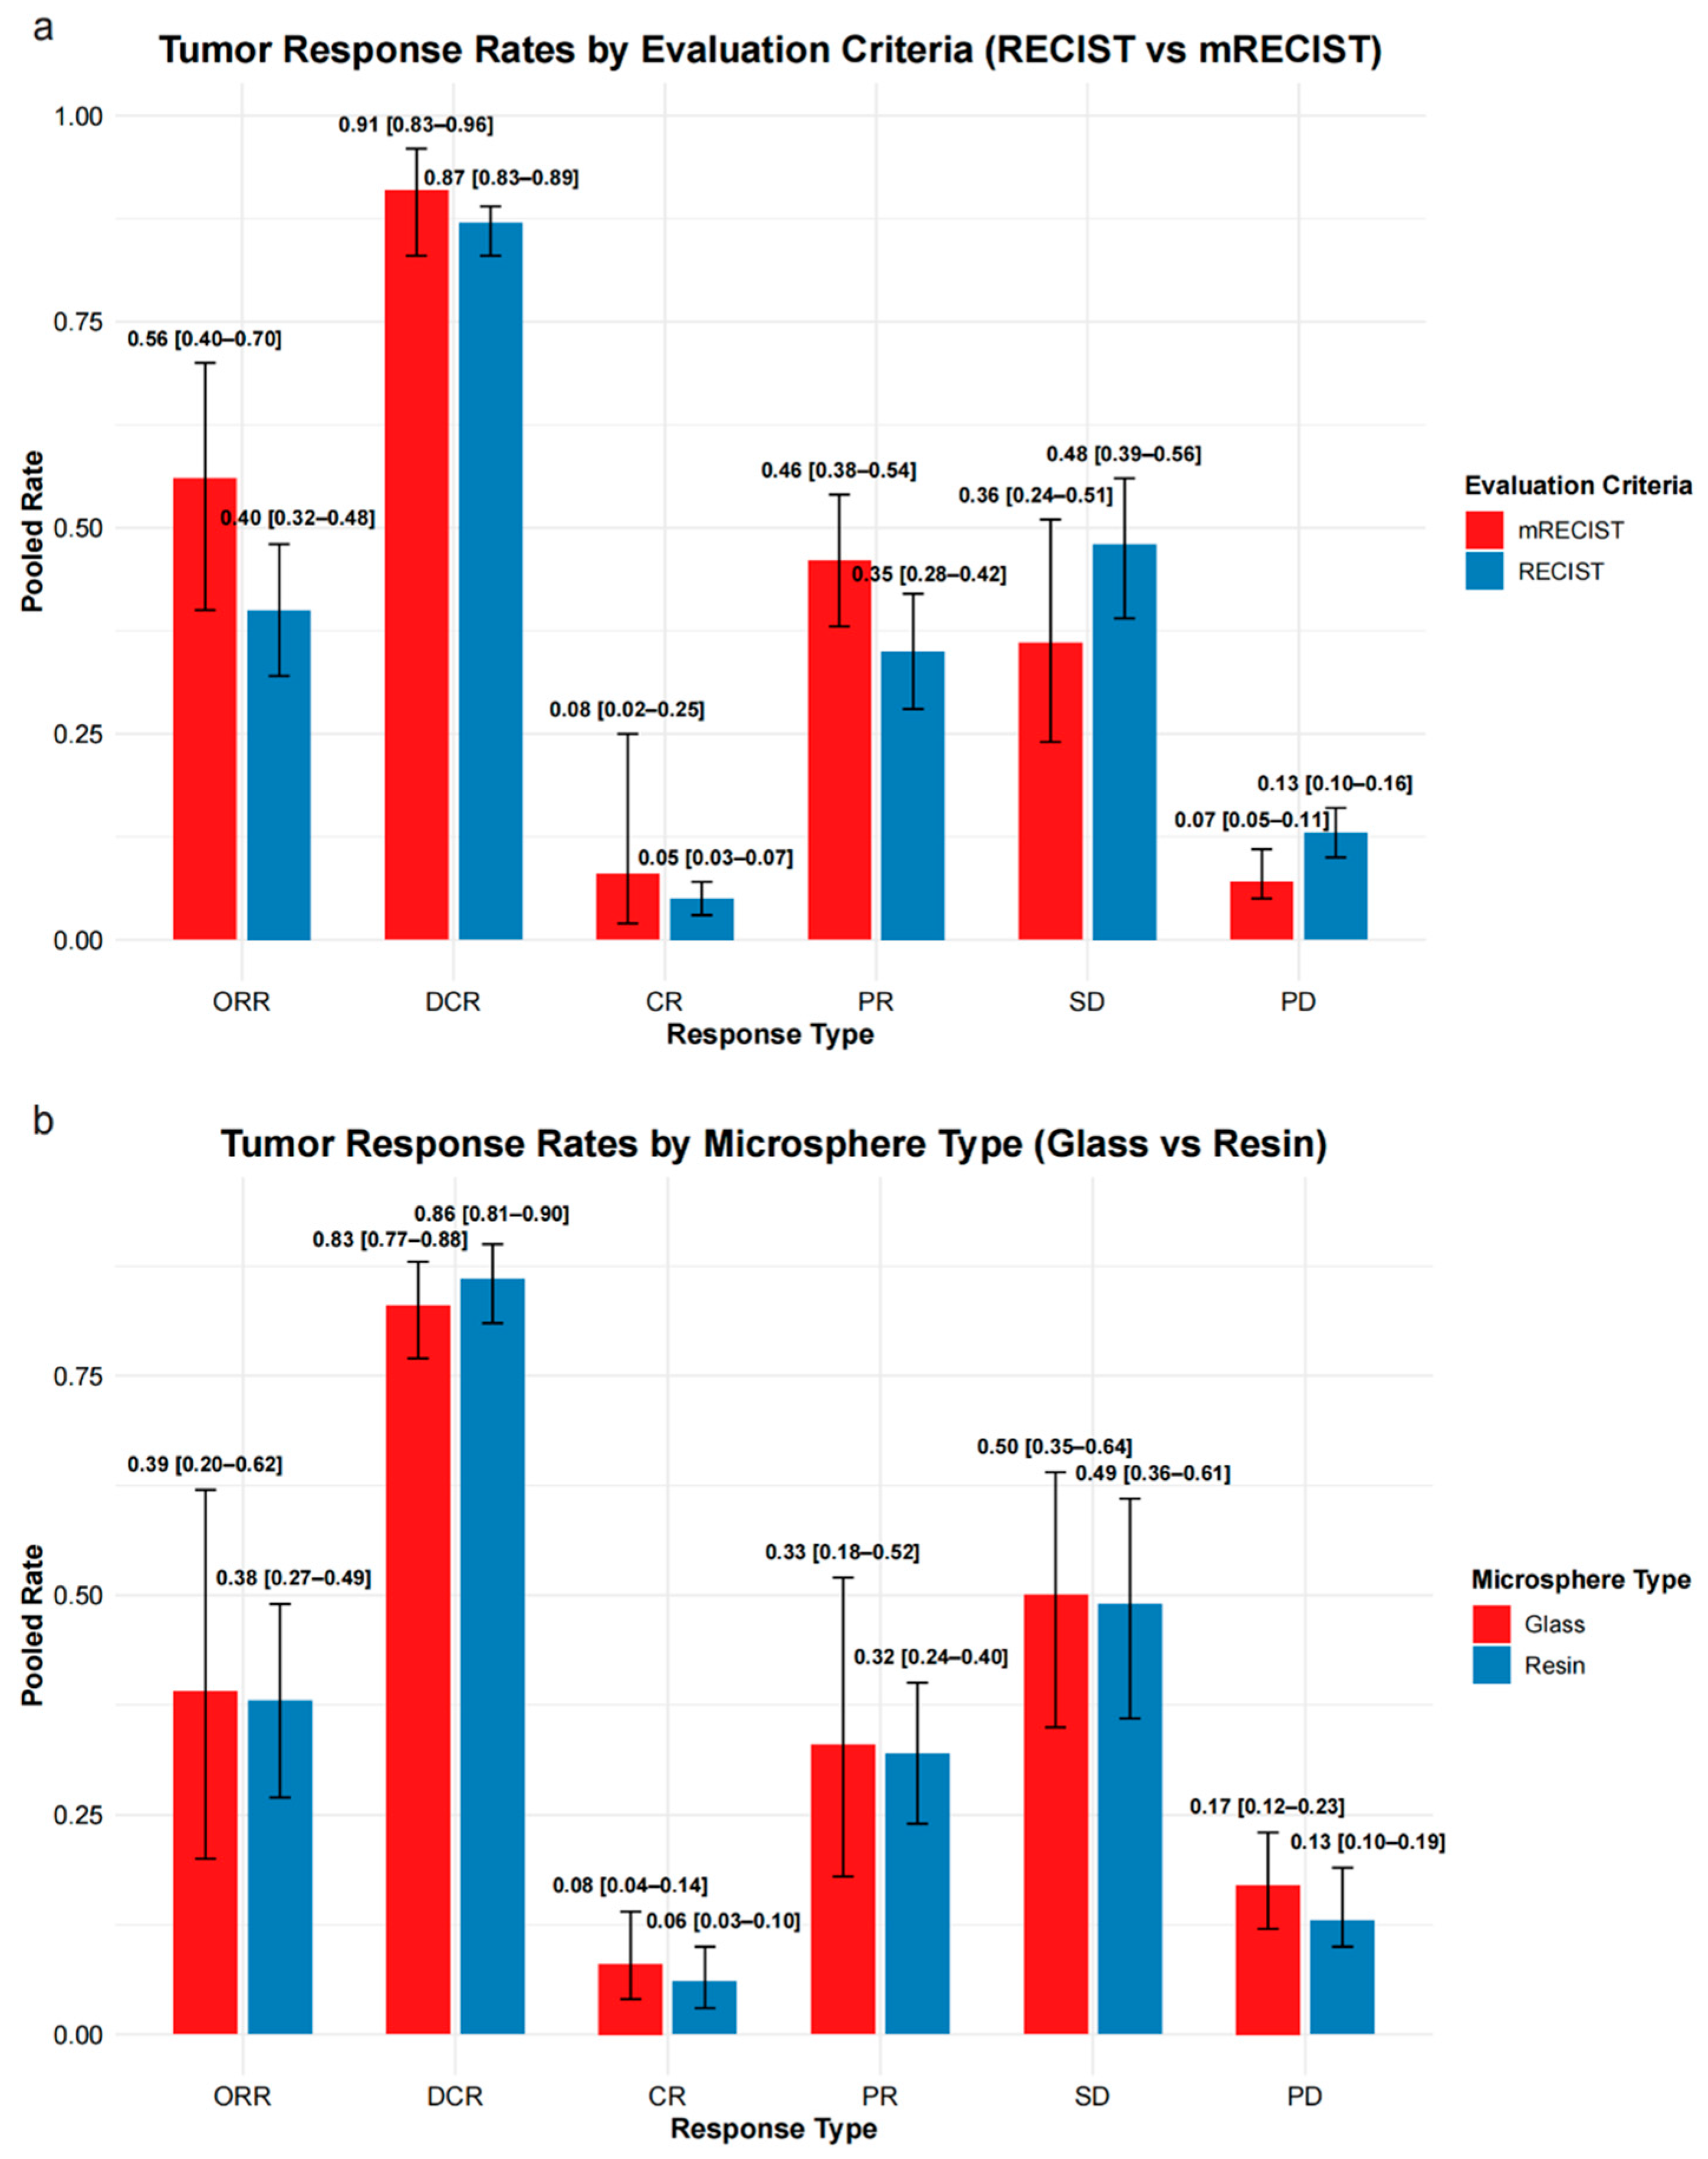

3.2.4. Tumor Response

3.2.5. Subgroup Analysis of Tumor Response by Microsphere Type

4.4. Refining Response Assessment: From RECIST to Whole-Liver Evaluation

4.5. Comparative Efficacy of Resin and Glass Microspheres